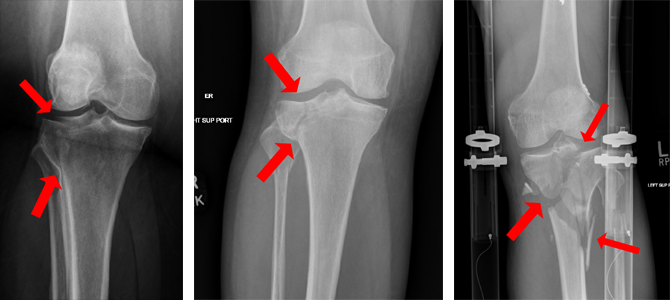

Figure 2: Knee X-rays illustrating a tibial plateau fracture.